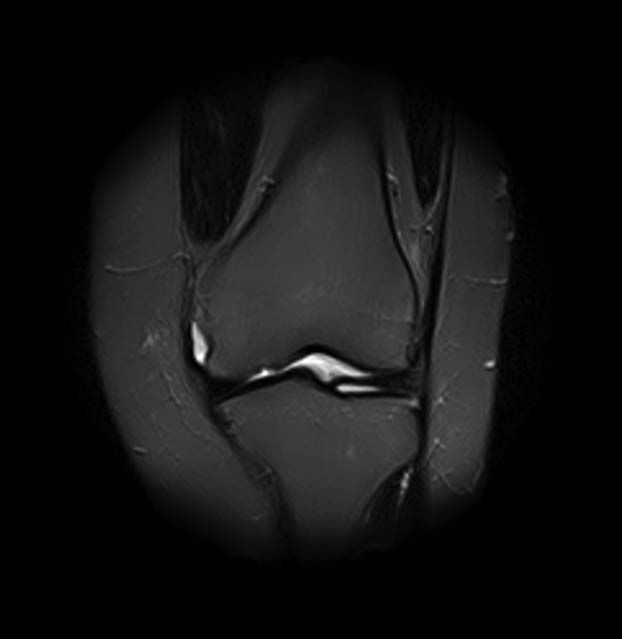

[Ortho] Показания для артроскопии

1. травма 5 лет назад - "ударилась коленом", с тех пор боли в суставе

3. стандартные рентгенограммы с небольшими изменениями - сужение

медиальной суставной щели

5. сустав клинически стабилен